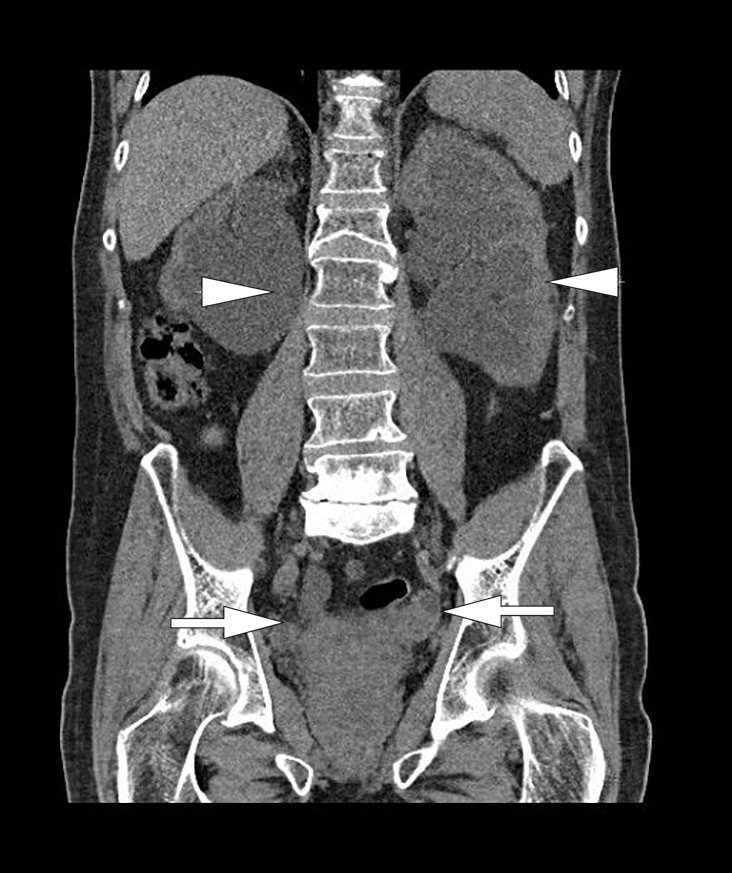

Like etter innleggelse ble det tatt CT urinveier uten intravenøs kontrast (fig 1). Denne viste bilateral uttalt hydronefrose og hydroureter med moderat atrofi av nyreparenkym. Det var forstørret urinblære med høyattenuerende innhold som ved blod. Cystoskopi ble gjort akutt og viste at blæren var fylt av koagler og papillomatøse tumorforandringer. Disse ble biopsert. Hematurikateter og bilaterale nefrostomikatetre ble anlagt. Biopsiene viste høygradig urotelialt karsinom, pT1GIII. Det ble ikke sett muskulatur. MR bekken viste uttalte tumorforandringer i nærmest hele blæren med innvekst i prostata og begge urinledere. Den viste også gjennombrudd av muscularis propria som ved minst T3-stadiet med muskelinvasiv blærecancer (fig 2, fig 3). For øvrig var det normale funn uten organmetastaser eller forstørrede lymfeknuter. Skjelettscintigrafi viste ikke tegn til metastaser. Ved nevropsykologisk testing fant man en sannsynlig mild kognitiv svik som ble planlagt fulgt opp etter utskrivning. Nyrefunksjonen bedret seg noe ved hjelp av avlastningen, og kreatininverdien stabiliserte seg rundt 190 μmol/l.